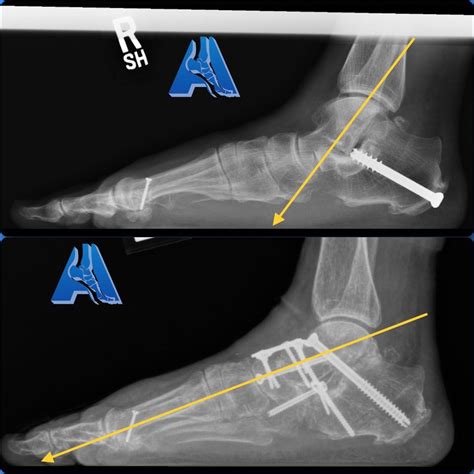

• Fixation: The bones are aligned and held in place using screws, plates, or rods. These fixation devices provide stability while the bones heal and fuse together.